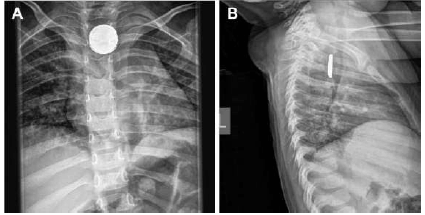

Paciente de 2 anos de idade é levada pela mãe ao hospital com relato de aumento de salivação subitamente, não conseguindo deglutir. A mãe relata que quadro iniciou há, aproximadamente, 1 hora após deixar a paciente sozinha na sala por alguns minutos, afirmando que antes a paciente estava bem. Foi realizada uma radiografia de tórax, obtendo-se a seguinte imagem.

Com base nesse caso clínico, assinale a alternativa que apresenta o corpo estranho ingerido pela paciente e a conduta a ser adotada nessa situação.